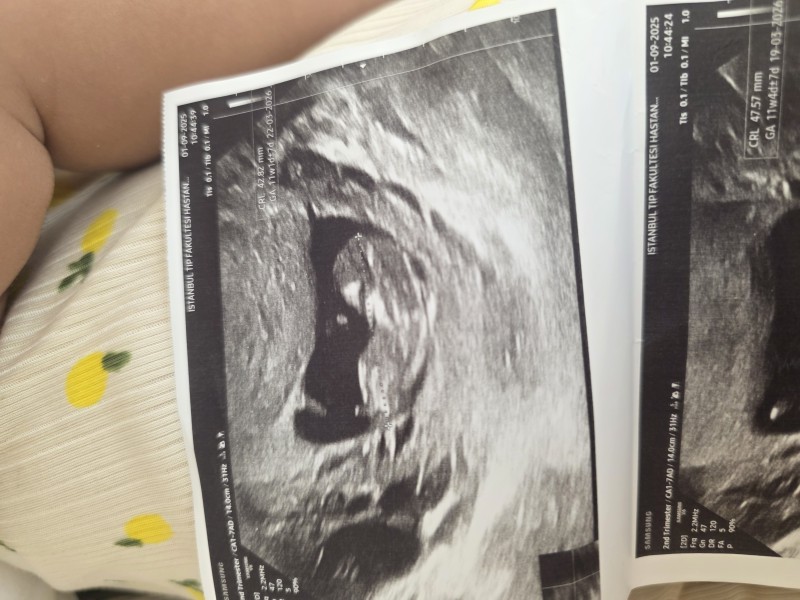

Ultrason görüntüsü güzel ama cinsiyet belli değil sizce neye benziyor

Erkek gibi hayırlısı olsun